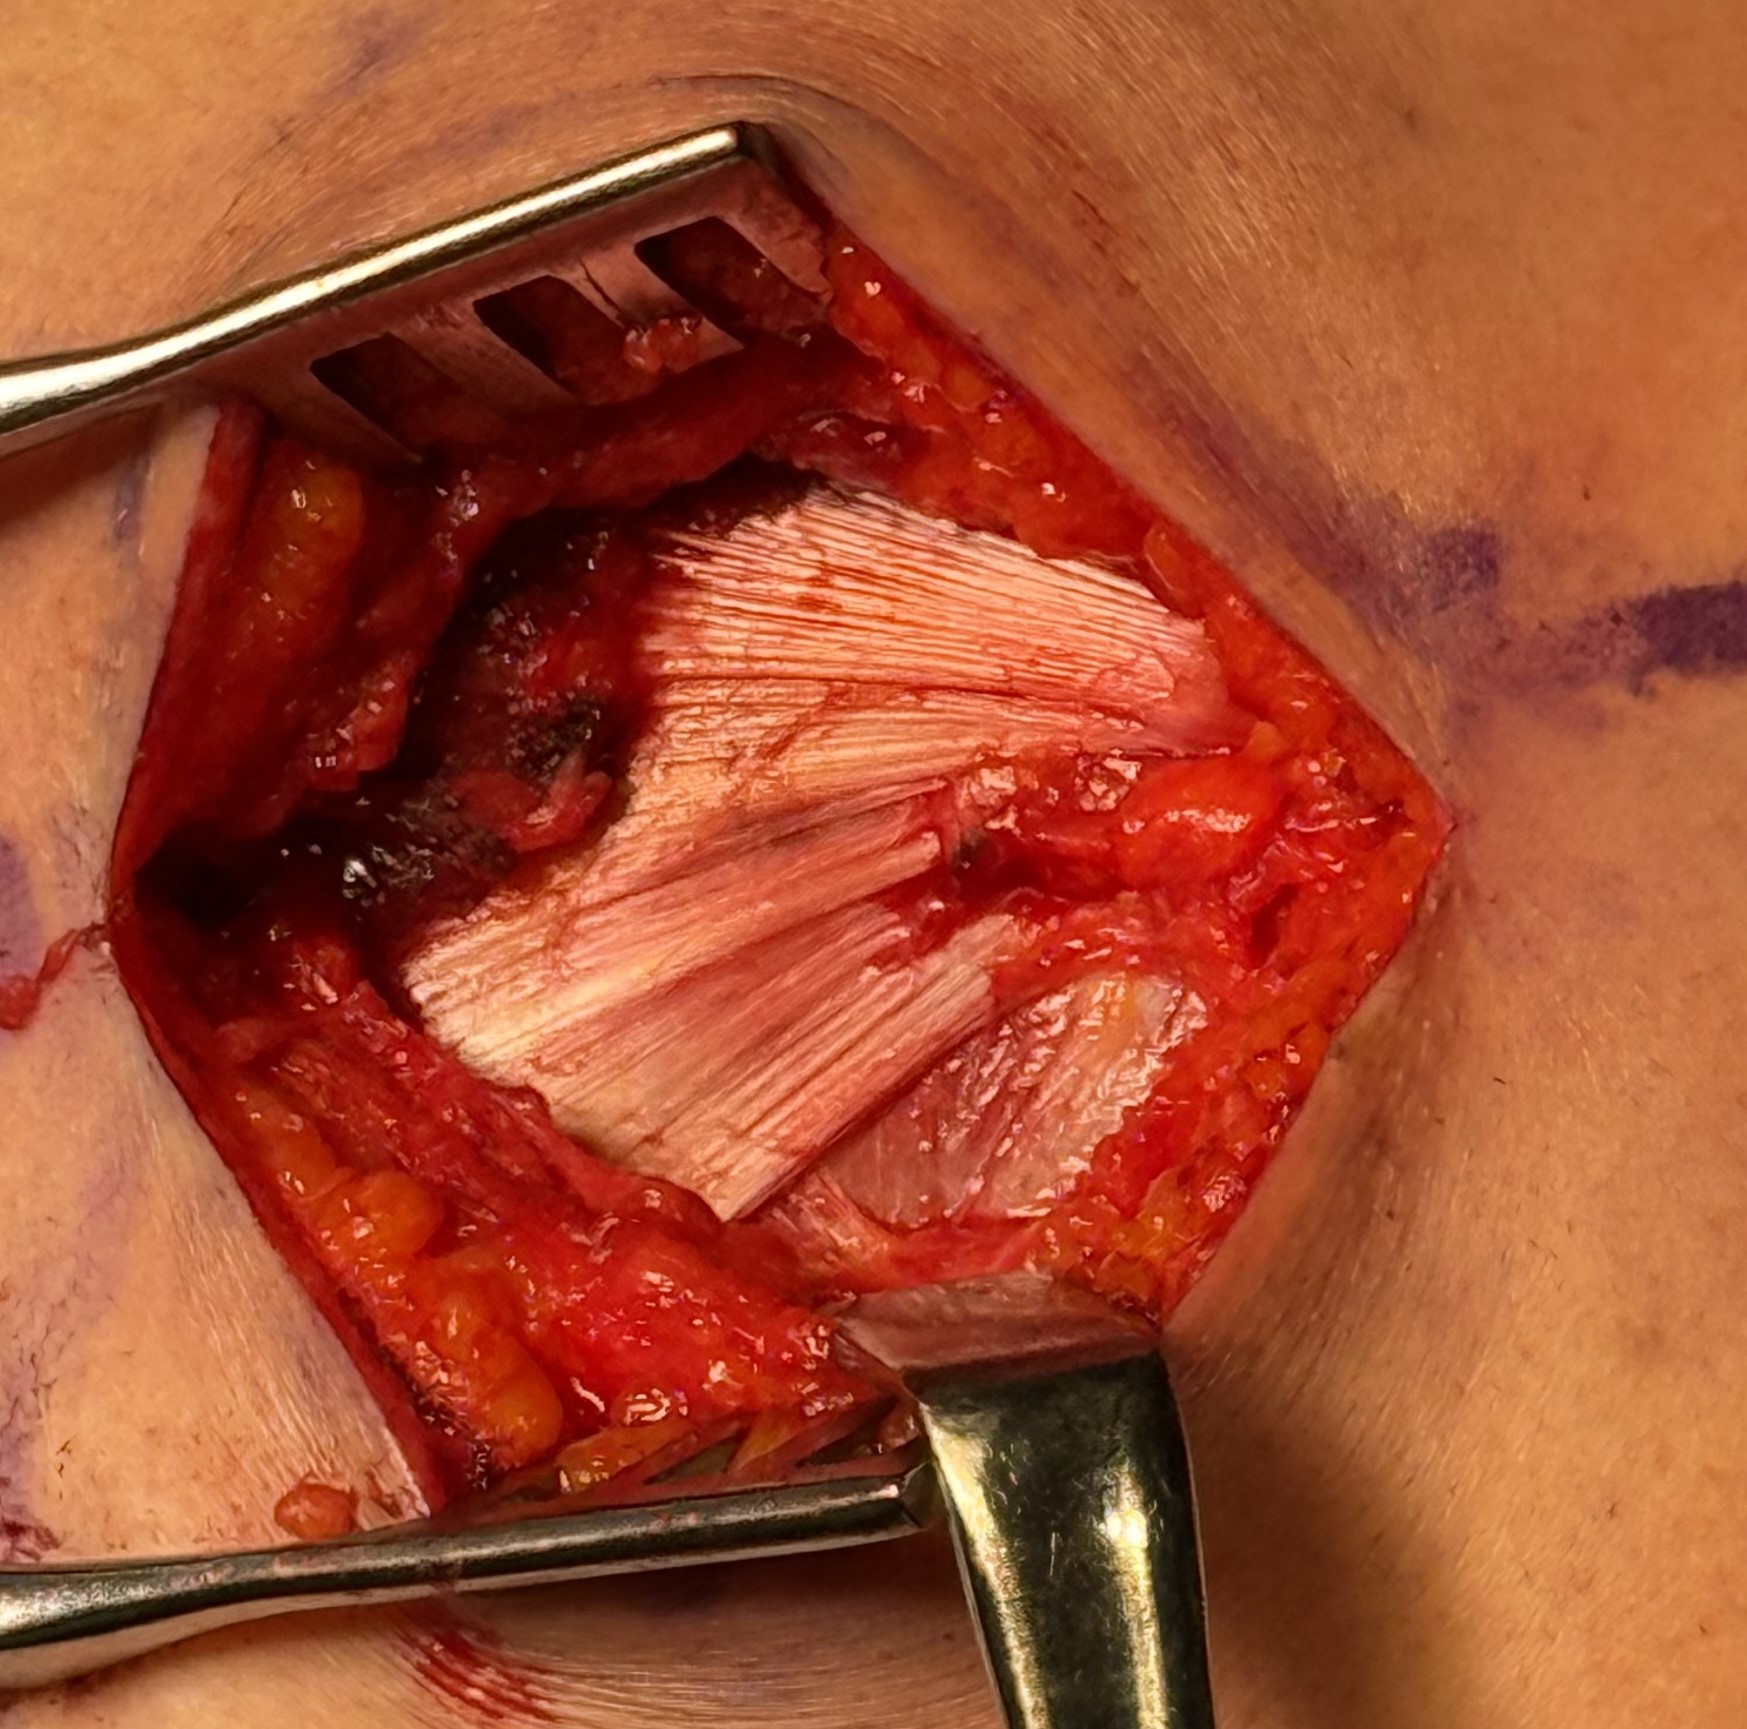

Technique

Margin convergence sutures

Release infraspinatus tendon posteriorly and assess mobility

Repair infraspinatus with a combination of margin convergence and posterior suture anchors onto posterior greater tuberosity

True partial repair of the rotator cuff with exposed triangle of greater tuberosity